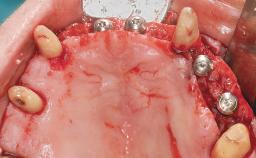

Defining Characteristics Fully edentulous upper jaw to be rehabilitated with four or more implants

Modality 6+ implants with immediate loading